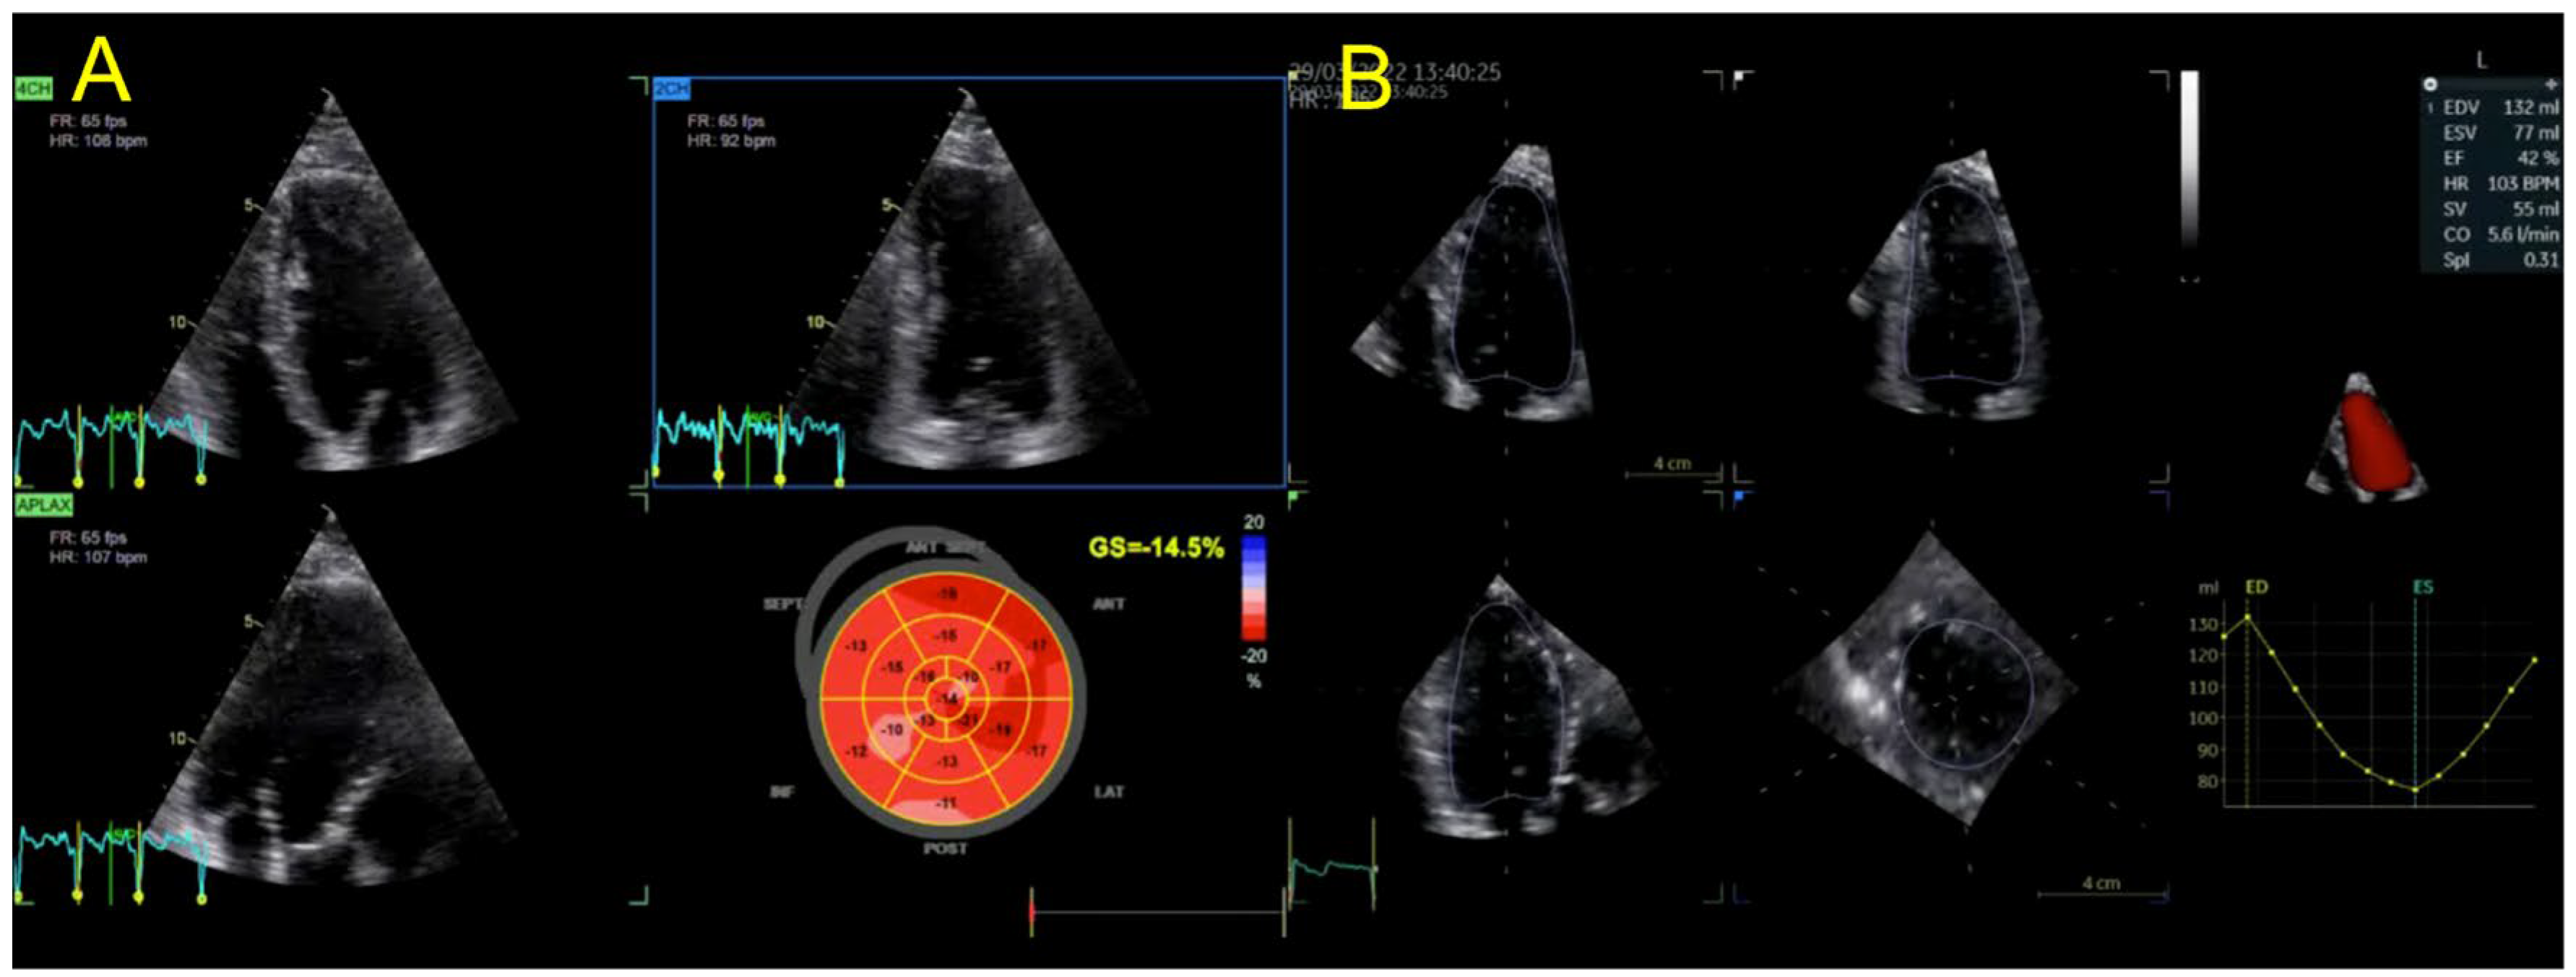

| Echocardiography | Hypokinetic non-dilated cardiomyopathy LVEF = 42% Mild mitral regurgitation IAS aneurysm | Hypokinetic non-dilated cardiomyopathy LVEF = 34% Mild mitral regurgitation IAS aneurysm | Left ventricular concentric hypertrophy LVEF = 54% |

| Cardiac magnetic resonance imaging | Hypokinetic non-dilated cardiomyopathy Left ventricular non-compaction LVEF = 50% | Hypokinetic non-dilated cardiomyopathy Regional sub-epicardial fibrosis LVEF = 41% | Not carried out |